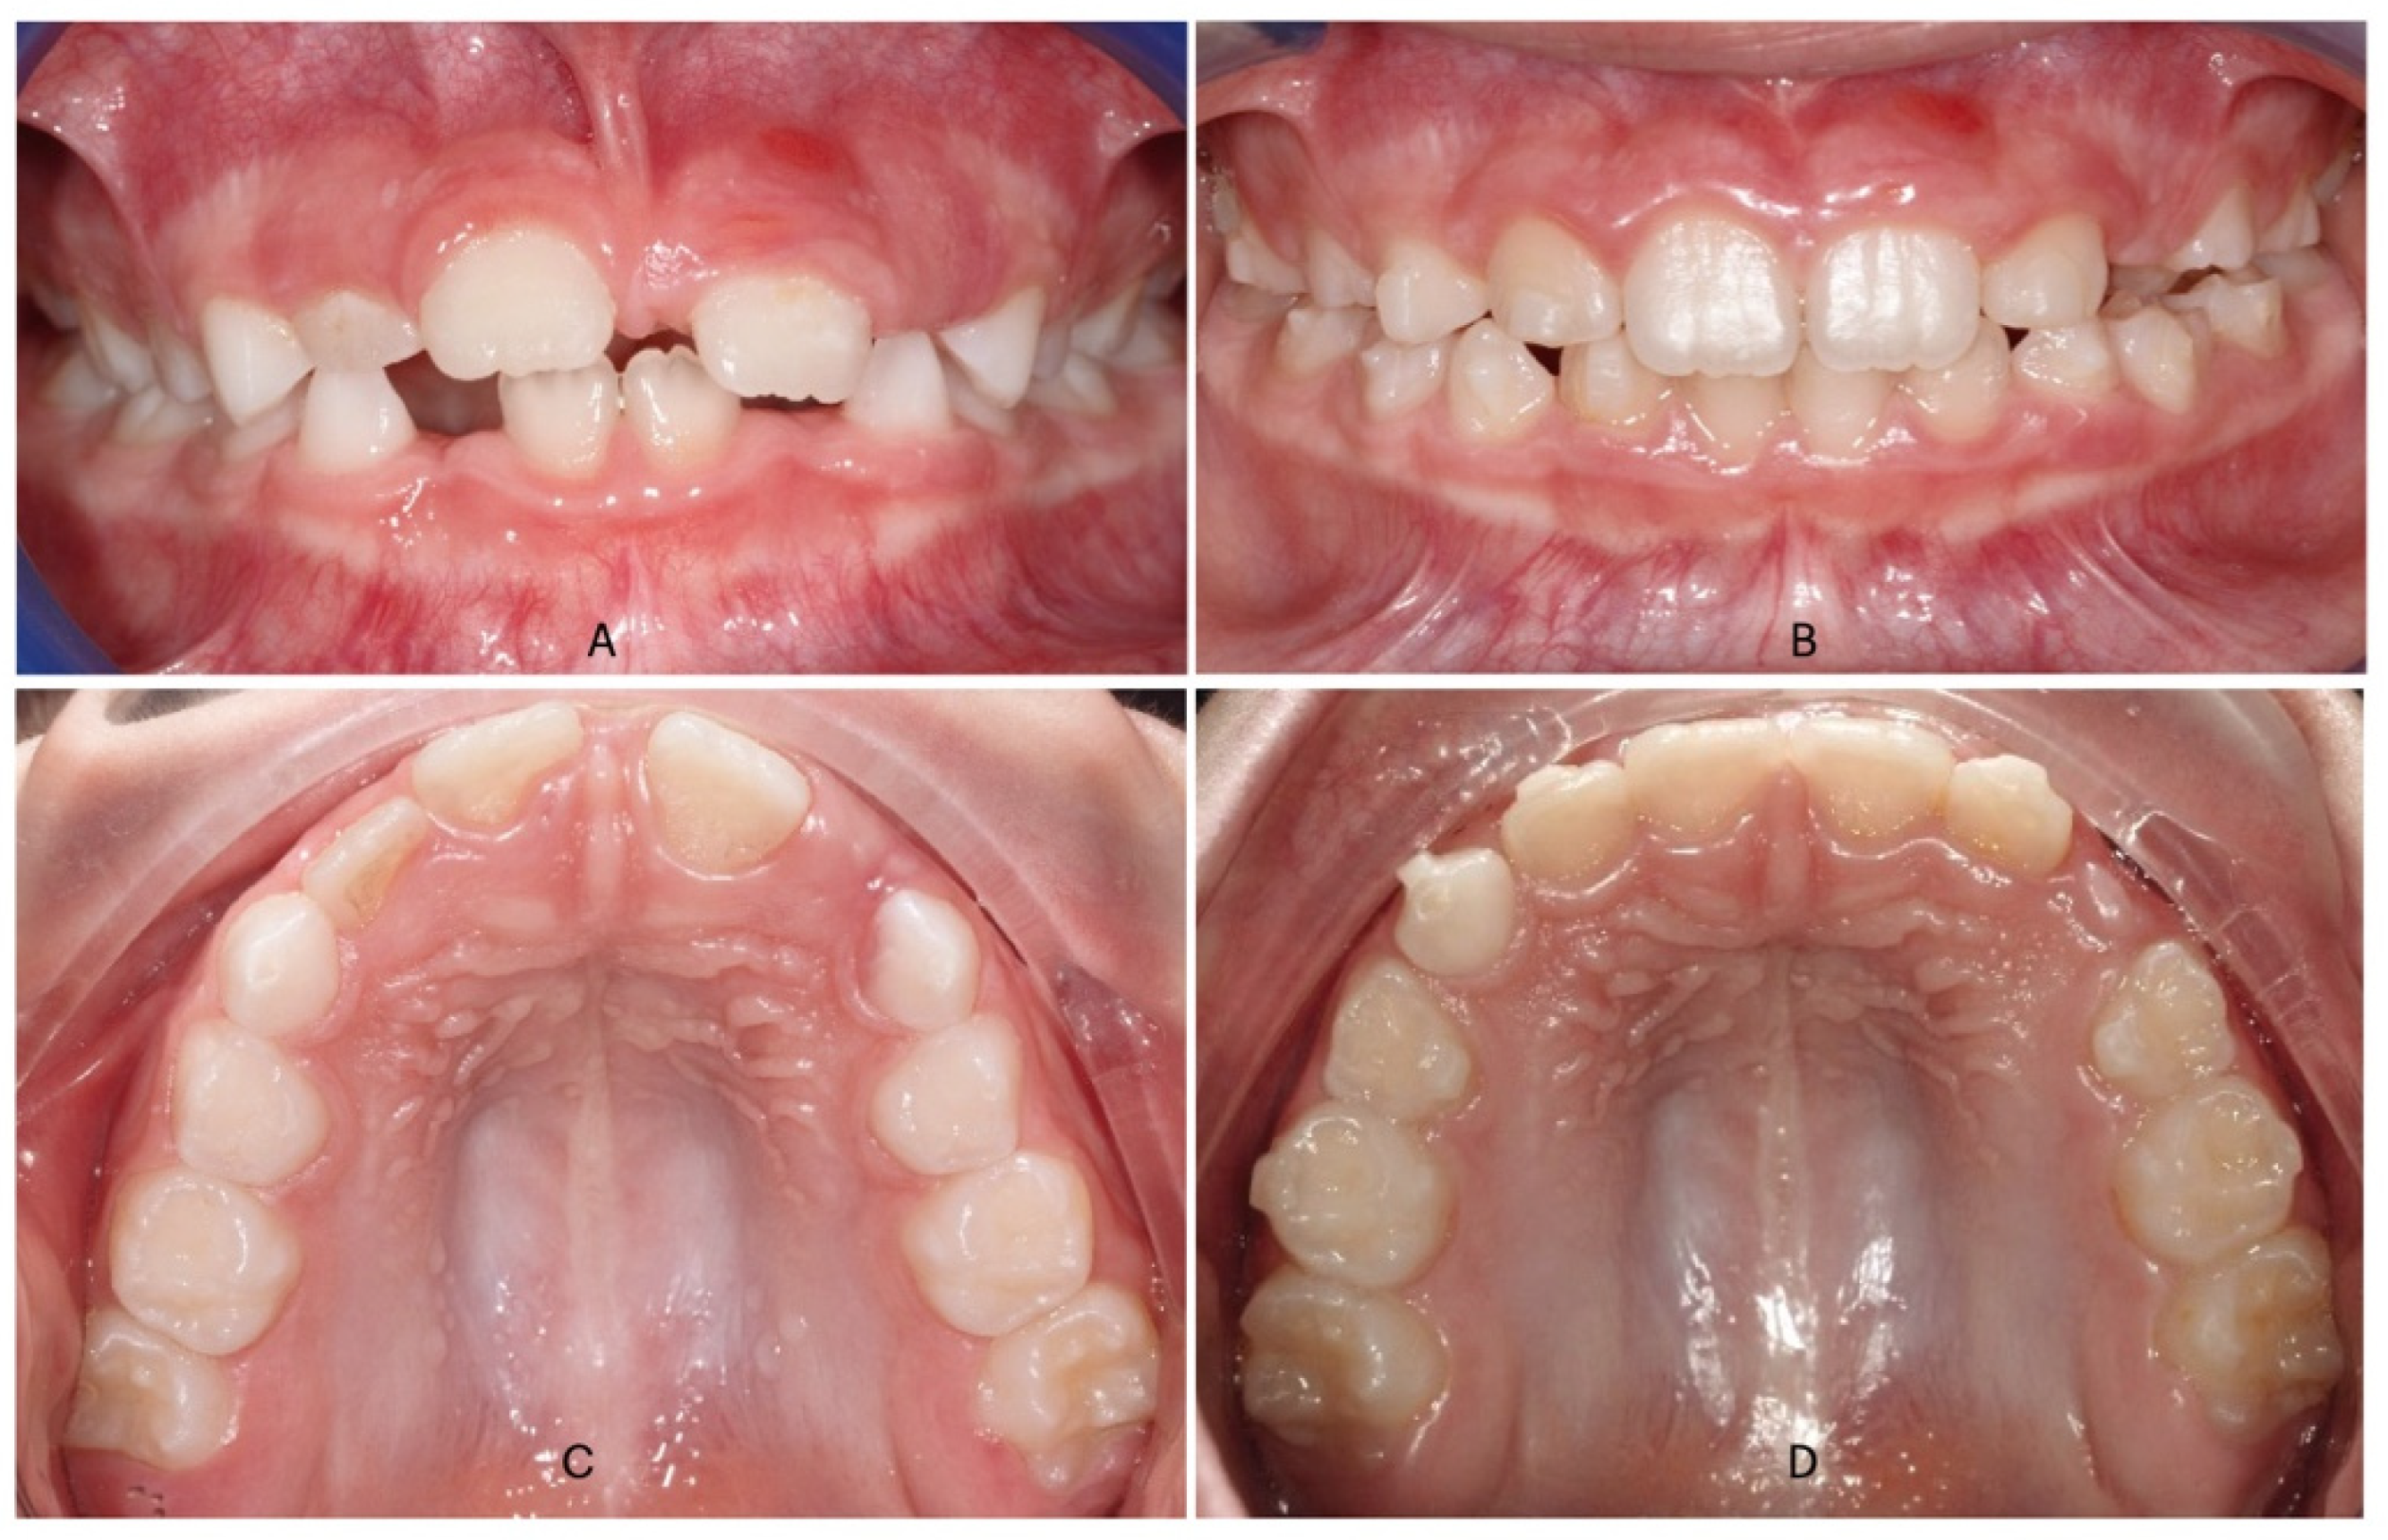

Intraoral scans of the upper and lower arch of all patients were taken before (T0) and after orthodontic treatment (T1) using the iTero scanner (iTero; Align Technology, San Josè, CA, USA). All digital dental models were downloaded as STL files and analyzed with Mimics Materialize 21.0 software (Materialize, Leuven, Belgium). A template consisting of points, lines, and planes of the upper and lower arch of the digital dental model was constructed within the software. The following reference points were identified (Figure 3): vestibular cusps of right and left upper deciduous canines, first and second deciduous molars and first permanent molars. In addition, McNamara amplitude was taken as distance between gingiva margins of palatal grooves of right and left first permanent molars (G16–G26) and compared to the distance in the lower arch between 3.6 and 4.6.

Figure 3.

Digital measurements taken from each digital model, before and after orthodontic treatment.